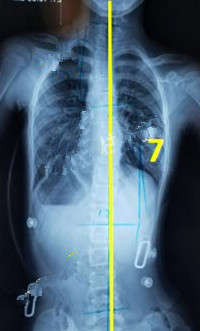

一般經過三個月至六個月的治療,對稱度都能得到改善,力線回正。

此時由于患者已經完全適應支具的力點,且體表變化較大,為了進一步矯正,我們需要對支具進行調整。如果由于孩子身高的變化較大,為了更進一步的矯正,可以考慮更換新的支具。

穿支具后